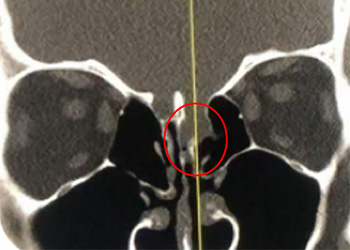

Endovascular:

Carotid Cavernous Fistula (CCF) Study

Author: Jonathan L. Brisman M.D., F.A.C.S., Read More!